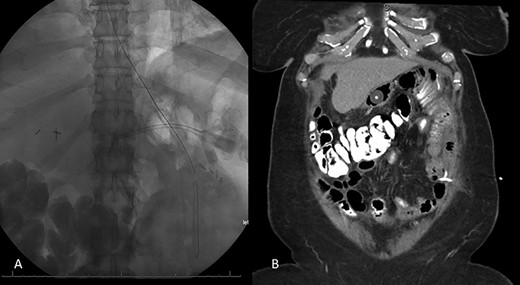

Decision was made to explore and attempt to excise the infarcted omentum. She was taken to the operating room and underwent a diagnostic laparoscopy. However, due to the large size of the omental infarction with an encapsulated necrotic liquefied, purulent secretion and significant adhesions, we decided to convert it to a midline laparotomy. We then proceeded with resection of right-sided infarcted, necrotic, liquefied omentum and abdominal washout (Fig. 3). Culture from the purulent secretion that was inside encapsulated omentum grew Streptococcus anginosus. She received Meropenem and Fluconazole. She had a prolonged and protracted recovery with a transient kidney injury and the development of multiple intra-abdominal (inter-loop, peri-hepatic, peri-splenic and pelvic) fluid collections (Fig. 4A). These collections were treated by percutaneous drainage (pelvis × 1, perisplenic and left-sided collections × 2). Three weeks from the take back, she developed a small bowel obstruction with significant dilation of the biliopancreatic limb and excluded stomach (Fig. 4B and C). She was taken to the operating room and had an endoscopically placed nasogastric tube just passed the jejunojejunostomy. Then, she underwent CT-guided gastrostomy tube to decompress in the gastric remnant (Fig. 5 A and B). One week after the rendezvous nasogastric and gastric remnant decompression, an oral and through the G-tube contrast study demonstrated patency of the gastrojejunostomy and resolution of the small bowel obstruction (Fig. 6). The patient was discharged home on POD #39 tolerating a regular postbariatric surgery diet.

Resolution of small bowel obstruction. A: Plain X-ray at POD # 25 from take back showing endoscopically placed nasogastric tube placement near JJ anastomosis B: Abdominal and pelvic CT scan showing percutaneous gastrostomy tube within the excluded stomach and pigtail catheter in the left hemiabdomen.